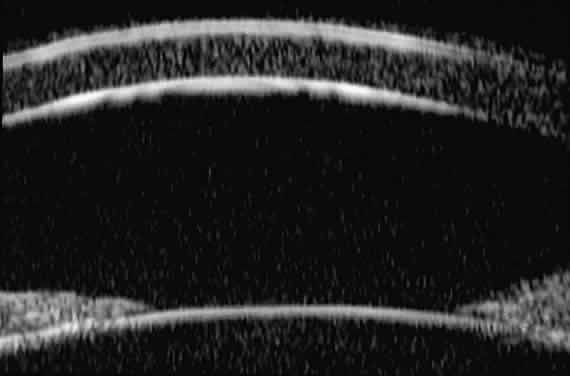

Ultrasound biomicroscopic slices through the mid-cornea and pupil (Fig. 3) show (1) the cornea, (2) the anterior chamber, (3) the lens, and (4) the pupillary zone of the iris. The cornea appears to have four well-differentiated layers. The epithelium is a thin, relatively bright (sonoreflective) layer. Just below that is Bowman's membrane, which appears as a highly reflective, very bright line. The stroma is the thickest layer and shows relatively homogeneous low-amplitude reflectivity. The endothelium and Descemet's membrane cannot be differentiated; together they form a single, highly reflective line at the posterior corneal surface. The aqueous in the normal anterior chamber appears completely sonolucent. The pupillary zone of the iris appears as two fingerlike structures consisting of a relatively sonolucent stroma and a bright posterior pigment epithelium. The anterior lens capsule appears as a bright retropupillary line. The normal anterior lens cortex appears nearly sonolucent.1–3

Fig. 3. UBM slice through mid-cornea and pupil of normal eye.

Radially oriented slices through the corneoscleral limbus (Fig. 4) show (1) the transition from cornea to sclera, (2) the anterior chamber angle structures, (3) the intermediate and peripheral zones of the iris, (4) the anterior ciliary body, (5) the equator of the lens, and, in some eyes, (6) the zonule. The corneoscleral junction is seen as an abrupt transition between the more sonolucent corneal stroma and the more sonoreflective sclera. The scleral spur can usually be identified as the most anterior extension of the deep sclera fibers at the limbus. The iris appears to consist of a relatively sonolucent stroma and a highly reflective pigment epithelium. The plane of curvature of the normal iris is smoothly bowed anteriorly. The insertion site of the iris relative to the scleral spur and anterior face of the ciliary body can be assessed. The pars plicata appears as fingerlike projections with acoustic features similar to those of the iris stroma. The ciliary sulcus is imaged between the peripheral iris and ciliary processes. The lens equator appears as a sonoreflective line (capsule) and underlying sonolucent stroma. Zonular filaments can be seen extending from the ciliary processes to the equatorial region of the lens in some eyes.

Fig. 4. Radial UBM slice through corneoscleral limbus of normal eye.

Radial, cross-sectional slices through the posterior ciliary body (Fig. 5) show the sclera as a highly reflective structure that can be easily differentiated from the underlying uveal and neuroepithelial layers of the pars plana. In most patients, UBM is not able to image the ora serrata, peripheral choroid, and peripheral retina.

Fig. 5. Radial UBM slice through pars plana of normal eye.

Additional slices through regions of interest can be obtained to evaluate specific features. For example, slices can be made through the pars plicata with the scanning plane concentric to the corneoscleral limbus (i.e., perpendicular to the previously made radial slices) (Fig. 6). Such images show the ciliary processes as a series of fingerlike projections.

Fig. 6. Transverse UBM slice through pars plicata of normal eye.